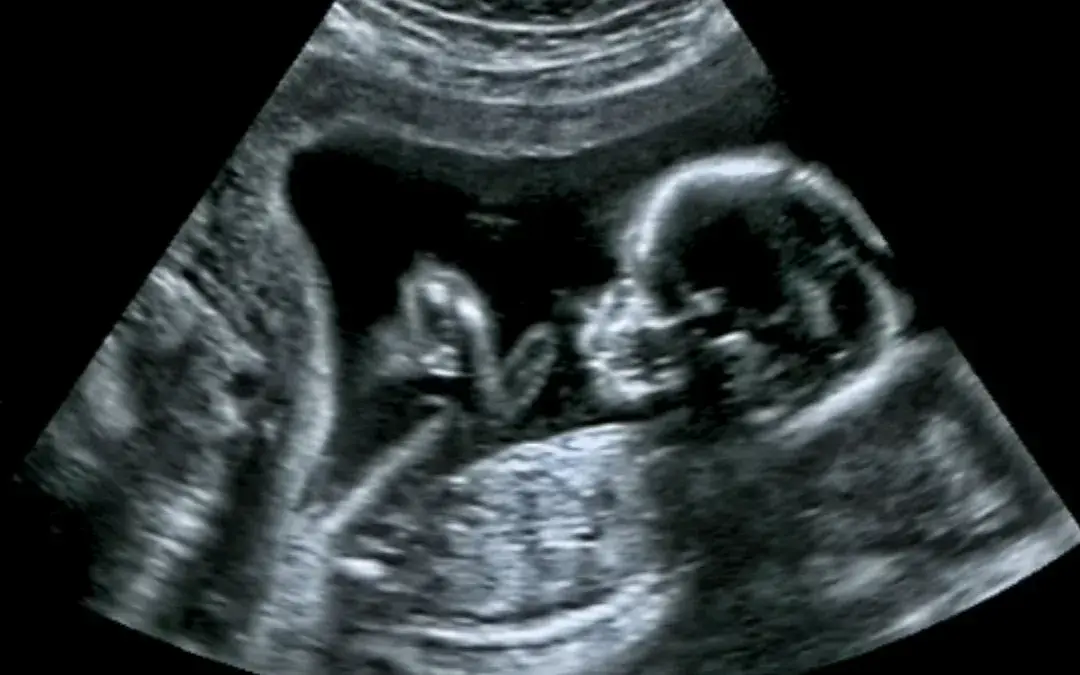

Pregnancy is a journey that requires proper medical care to ensure the healthy development of the baby. One of the most important prenatal tests is the ultrasound, a non-invasive procedure that uses high-frequency sound waves to generate images of the developing fetus. A level 2 ultrasound, also known as a detailed fetal anatomy scan, is a specialized ultrasound that provides more detailed information about the baby’s development. In this article, we will discuss everything you need to know about level 2 ultrasound.

This ultrasound is usually performed during the second trimester of pregnancy, i.e., between weeks 18 and 22. Unlike a level 1 ultrasound, which is primarily used to confirm a healthy pregnancy, estimate the due date, or determine the age and location of the fetus, a level 2 ultrasound provides more detailed information about the development and well-being of the fetus. This includes a closer examination of the fetal organs, amount of amniotic fluid, brain, spine, limbs, and other structures.

The procedure provides detailed images of the baby’s organs and tissues, allowing healthcare providers to detect any abnormalities.